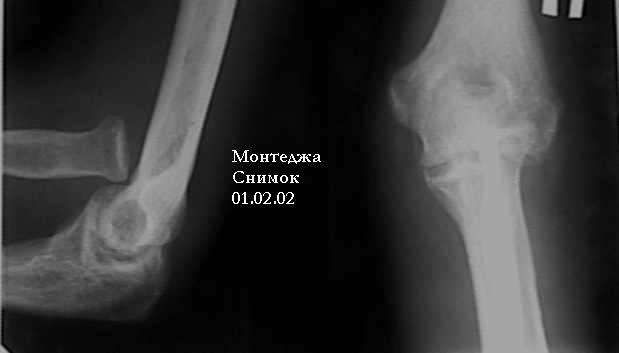

У больного травма в октябре 2001. Перелом Монтеджа разгибательный.Проведена операция металлостеосинтез пластиной, винтами локтевой кости. Вывих головки лучевой кости не диагностирован. В конце февраля 2002 г снята гипсовая повязка. Имеется ограничение сгибания до 115 градусов. Больной обратился в наше лечебное учреждение 07.02.02. Мы предложили ему оперативное лечение. Планируем провести резекцию головки лучевой кости. Есть мнение попытаться вправить головку лучевой кости, провести пластику кольцевидной связки, фиксисировать головку лучевой кости трансартикулярно спицей. Но боюсь, что в момент остеосинтеза была укорочена локтевая кость, поэтому необходимо будет провести резкцию в области диафиза лучевой кости, а затем провести остеосинтез лучевой кости. Рентгенограммы:

1; 2; 3; 4